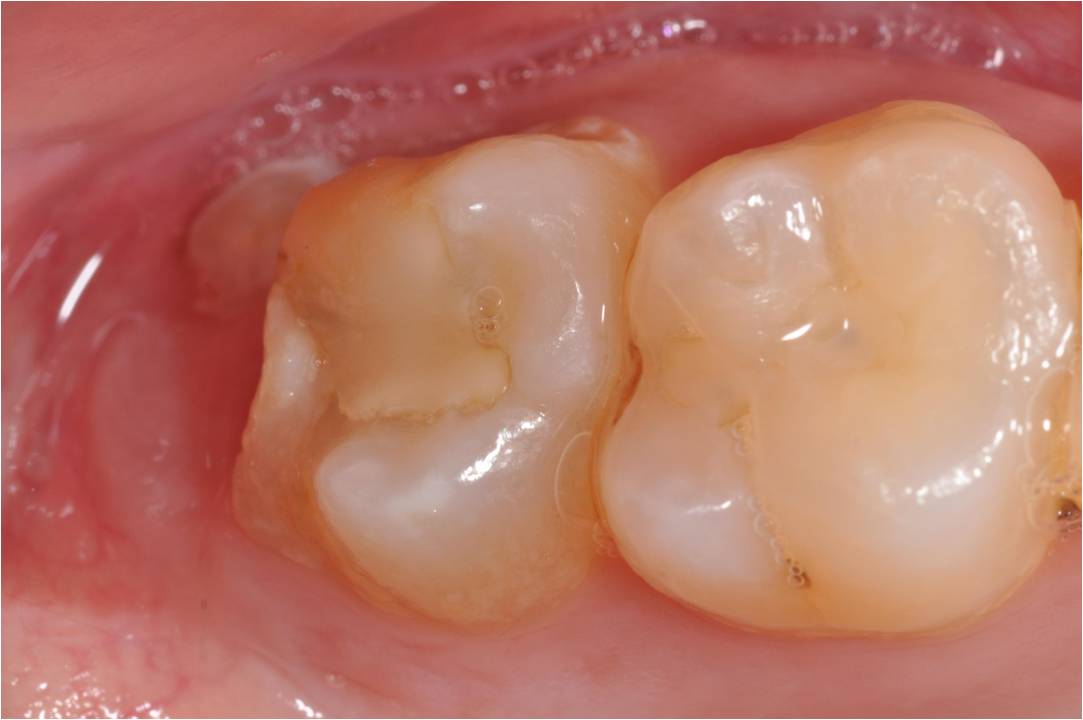

治療前,已補上複合樹脂,二次蛀牙,牙齒敏感